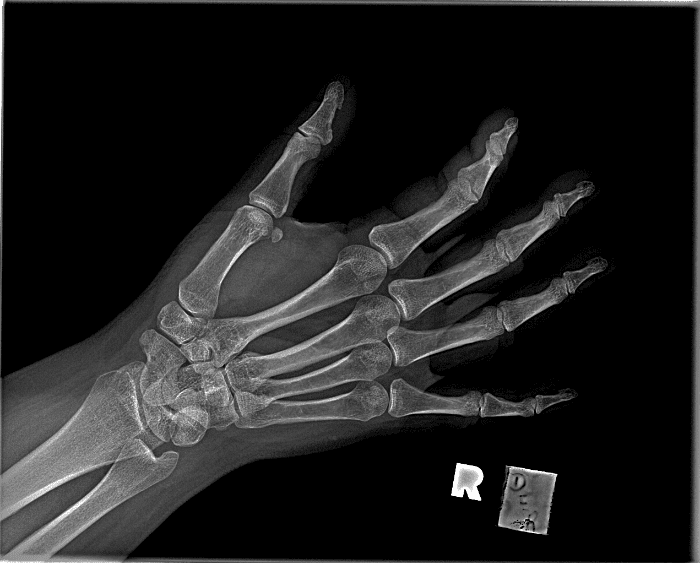

Simuliert den Dienst durch subtile oder schwierige Fälle und einige Normalbefunde.

30 Fälle